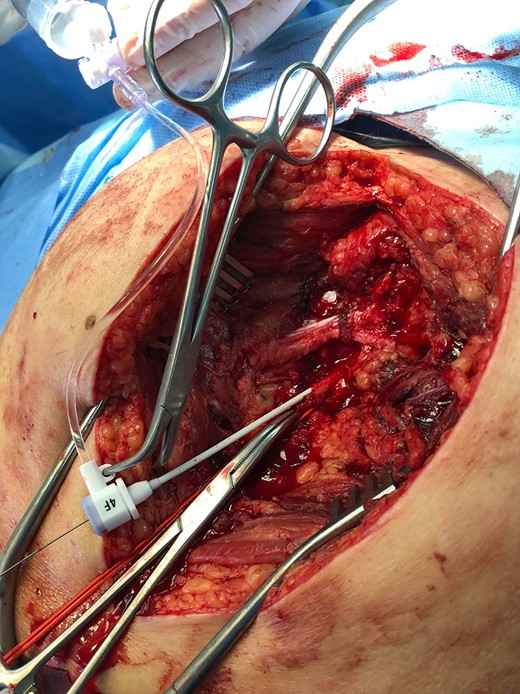

Under general anesthesia the patient was placed in prone position and a 15 cm transverse incision, slightly curvy was performed in the middle part of the right gluteal region between the posterior superior iliac spine and ischiac tuberosity. The gluteus maximus muscle was split and the inferior gluteal artery was identified as it entered the gluteal region through the greater schiatic foramen near the schiatic nerve below the piriformis muscle. The inferior gluteal artery was punctured using Seldinger technique and a 4Fr was introduced into the artery (Fig. 2). An angiography was made revealing the aneurysm of the right IIA and two feeding arteries, inferior gluteal artery and probably a branch of superior gluteal artery, filling the sac (Fig. 3). A 0.014 inch Pilot guide wire (Boston Scientific Corporation, USA) was inserted into the aneurysm and a microcatheter 3 Fr RENEGADE STC (Boston Scientific Corporation, USA) was advanced over the wire. After removing the wire, embolization microcoils (Interlock, Boston Scientific, USA) (two coils 22–600 mm, two coils 20–500 mm, three coils 18–500 mm) were introduced into the aneurysm sac (Fig. 4). A 5 Fr sheath was subsequently placed, a 5Fr RIM catheter (Cordis, USA) was advanced to the aneurysm sac through a 0.035 inch Terumo guide wire (Glidewire, Terumo Corporation, Japan) and selective catheterization of the second feeding artery was performed (Fig. 5). Embolization coils (Interlock, Boston Scientific, USA) were inserted into the two feeding arteries (two coils 15–400 mm) (Fig. 6). Completion angiogram depicted absence of blood flow into the aneurysm and the runoff vessels (Fig. 7). The patient had an uneventful recovery period without buttock claudication, ischemic complications and discharged in good condition. A follow-up CT aortography after 6 months depicted complete thrombosis of the aneurysm (Fig. 8).

Posterior surgical access to the aneurysm, a sheath is inserted in the inferior gluteal artery.